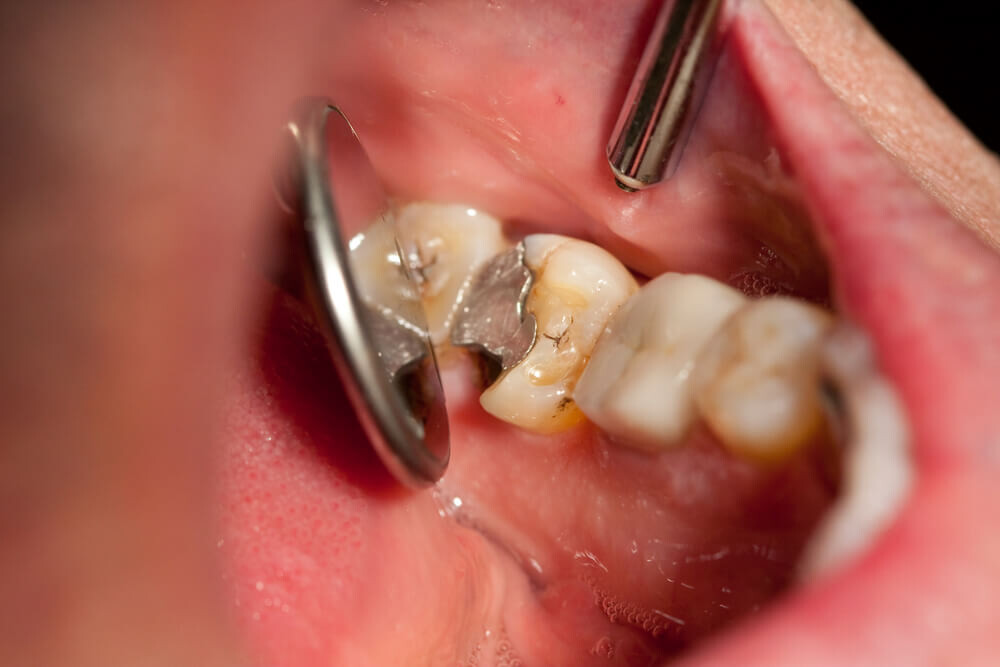

Tooth decay

As tooth decay progresses, it can reach the softer inner layers of the tooth, called dentin and pulp, resulting in sensitivity to hot, cold, or sweet foods and drinks and eventually leading to a toothache. If left untreated, tooth decay can result in an abscess, a painful infection at the root of the tooth that can cause severe pain and swelling. Adhering to your routine dental check-ups, practicing good oral hygiene, and eating a healthy diet can help prevent tooth decay and the resulting toothache.

Abscessed tooth

An abscessed tooth occurs when the pulp inside your tooth becomes infected, typically due to decay or damage. The infection can spread to the tooth’s root and surrounding tissues, causing pain and swelling. In some cases, a pocket of pus may form in the affected area, leading to additional discomfort and even fever. Abscessed teeth may also cause sensitivity to hot or cold foods, a bad taste in your mouth, and difficulty chewing or speaking. If you have an abscessed tooth, inform your provider to prevent further complications and potential tooth loss.

A damaged filling

A damaged filling can cause toothache when the filling is no longer able to protect your tooth from external stimuli. When a filling is damaged, it can create an opening in the tooth, allowing bacteria to penetrate and cause an infection, leading to inflammation, swelling, and pain. Additionally, if you don’t replace the filling in time, it may cause your tooth to weaken or crack. A damaged filling may also cause sensitivity to hot and cold food and drinks.